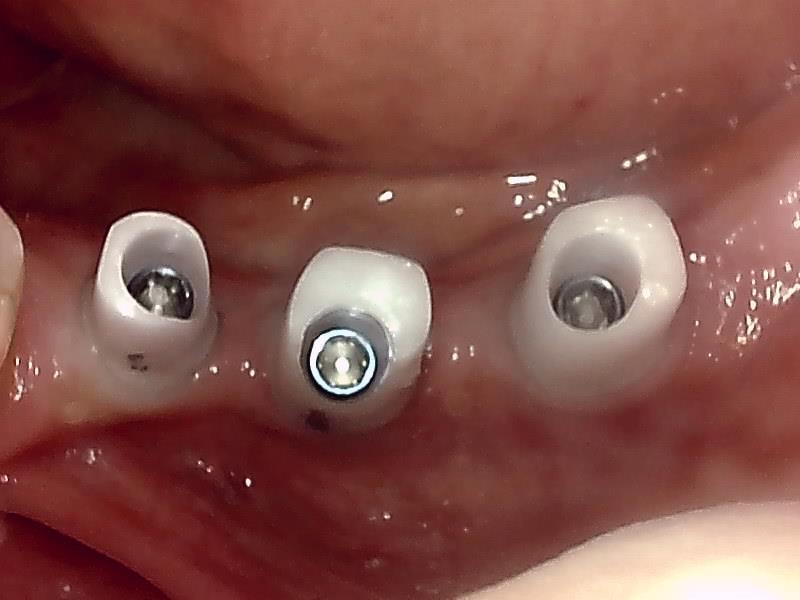

アバットメント装着 (左下)

(ジルコニアアバットメント)

(ジルコニアアバットメント) (咬合面観)